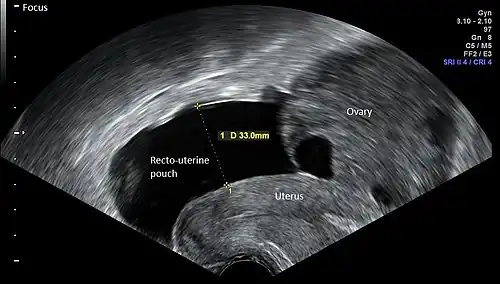

![]() ![]() Vaginal ultrasonography in the sagittal plane in a woman with mild OHSS, showing a 33 mm wide anechogenic area behind the uterus in the recto-uterine pouch, which means there was ascites, that is, free fluid in the peritoneal cavity. Normally, there is up to 5 ml of fluid in the recto-uterine pouch,[5] corresponding approximately to an area up to 10 mm wide. The ovary measured up to 6.5 cm in diameter. |